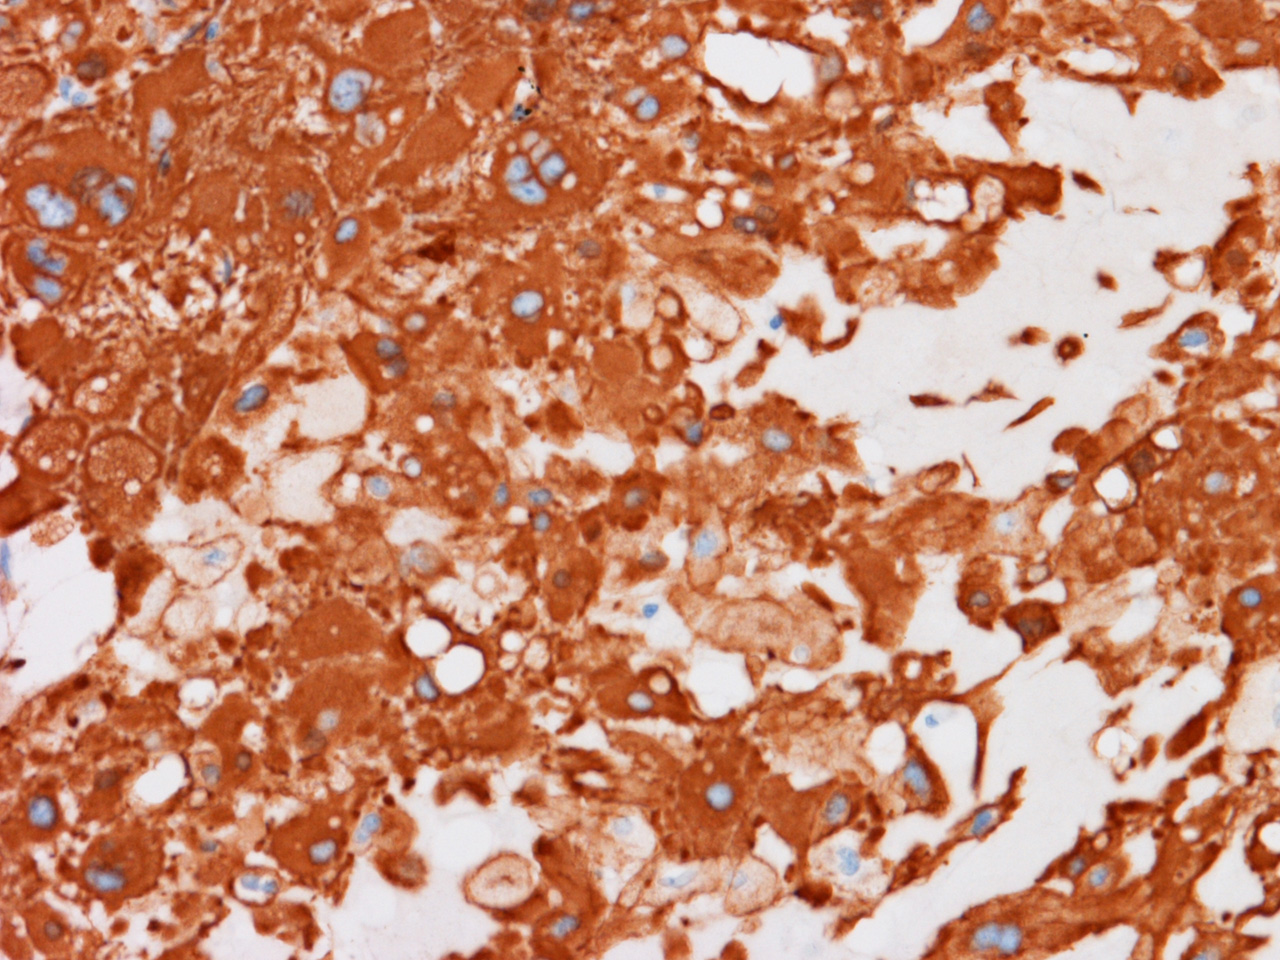

At the time of operation, a cytologic squash preparation (H&E) was prepared (Panels BC, and D). On low magnification, the lesion is composed of large clusters of eosinophilic cells with centrally located nuclei. There is some bluish acellular substance admixed with the tumor cells (Panel B). If you pay attention, some of the cells are arranged in short chains (arrows in Panel C). This is a frequently seen phenomenon in chordoma. On high magnification, the cells have centrally located medium sized to large, hyperchromatic nuclei. The cytoplasm is finely eosinophilic but not particularly bubbly  (Panel D). The frozen sections (Panels E and Freflect the cytologic features. The tumor is composed of solid sheets of large tumor cells admixed with small amount of fibrous areas, mild chronic inflammatory cell infiltration and hemosiderin depositions (Panel E). On high magnification, the tumor cells are admixed with bluish extracellular material.  The cytoplasm is coarsely granular with fine bubbles. The permanent sections (Panel G and Hshow similar features. And the bubbly cytoplasm is more prominent in the permanent sections (Panel H). Focal bone invasion is present (Panel I). The cytoplasmic vacuoles are best appreciated in the semithin section (Panel M). Results of special studies are as follows:

On immunohistochemistry, nuclear expression of brachyury (a T-box transcription factor encoded by the TBXT gene involved in notochordal development) is a highly specific marker when the clinical and histopathologic features are taken into consideration [Miettinen M et a., 2015Oakley GJ et al., 2008Vujovic S et al., 2006Sangoi AR et al., 2011Clayton EF et al., 2013]. With this said, one must note that nuclear expression of brachyury is also expressed in about three quarter of the cases of embryonal carcinoma, half of the cases of seminoma and a minor proportion of yolk sac tumor, and 41% of small cell carcinoma [Miettinen M et a., 2015]. Brachyury is also expressed in the cytoplasm of intracranial hemangioblastoma [Barresi V et al., 2012] but not in peripheral hemangioblastoma [Doyle LA & Fletcher CD, 2014], primary carcinoma of lung [Haro A et al., 2013], prostate cancer [Pinto F et al., 2014], and colorectal carcinoma [Kilic N et al., 2011]. Although brachyury is usually positive for chordoma, immunoreactivity can be lost in decalcified tissues, and it is not typically expressed in the dedifferentiated component of dedifferentiated chordomas.

Chordomas are typically positive for brachyury, pan-cytokeratin, epithelial membrane antigen, SOX9, SHH, cathepsin K, and cadherin. Although the combination of characteristic morphology with strong positivity for pan-cytokeratin are diagnostic for chordoma until proved otherwise, one must note that chordomas are typically negative for cytokeratin 7 and cytokeratin 20 [Folpe AL et al., 1999]. Expression of cytokeratin 18 is variable.   Chordoma is variably positive for S100. This is different from chondrosarcoma where S100 is typically evenly and strongly expressed. Ki67 labeling is moderate to high. This is an important features to distinguish chordoma from benign notochordal cell tumor and ecchordosis physaliphora/fetal vestige [Amer and Hameed, 2010].